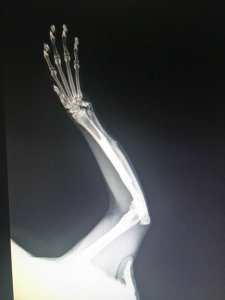

Gute Nachrichten. Jokers Platte kann vorerst drin bleiben. Auf dem Röntgenbild sieht alles sehr gut aus. Die Fraktur, die er sich zusätzlich unter der Platte zugezogen hatte, ist einwandfrei verheilt. Der Knochen über der Platte wächst schön gerade. Ich soll nur darauf achten, ob Jokers Körper die Platte nicht doch irgendwann abstößt, dann muss sie natürlich raus. Aber bis dahin heißt es Gott sei Dank „keine Boxenhaft für den kleinen Racker“.

Genau so hatte ich mir das gewünscht. Nach Fund und Operation hatte Joker Probleme, auch mit

Giardien. Ein längerer stationärer Aufenthalt war darum erforderlich. Ich hatte Sorge, dass die bei einer erneut nötigen Op und dem damit verbundenen Stress wieder auftreten könnten. Darum soll er auch weiter auf der Pflegestelle mit seinen beiden Onkels Bobby und Sammy leben.